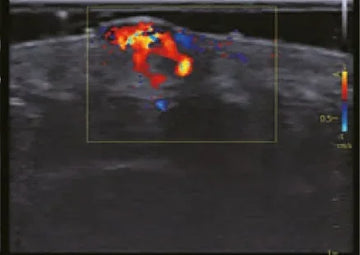

Para o scanners de ultrassom , os Manutenção preventiva de aparelhos de ultrassom É essencial. Envolve a inspeção regular dos transdutores, do sistema de processamento de imagem, dos cabos e do software. Com que frequência um aparelho de ultrassom deve ser revisado ? A frequência ideal varia dependendo do uso e do tipo de equipamento, mas uma revisão anual é uma boa prática para identificar desgastes ou mau funcionamento antes que se tornem avarias dispendiosas. Esse cuidado proativo não só maximiza a vida útil do equipamento, como também garante a consistência e a confiabilidade dos diagnósticos por ultrassom.